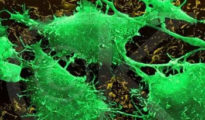

La enoxacina, el freno al crecimiento del cáncer

Científicos del Instituto de Investigación Biomédica de Bellvitge (Idibell) han identificado una sustancia , llamada ‘enoxacina’, que inhibe el crecimiento del cáncer mediante su acción en la...